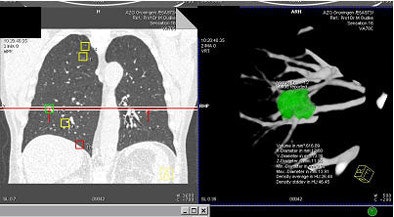

![]() |

| Above and below: a solid nodule measuring 617 mm3, was confirmed as lung cancer. Images courtesy of Dr. Rozemarijn Vliegenhart. |